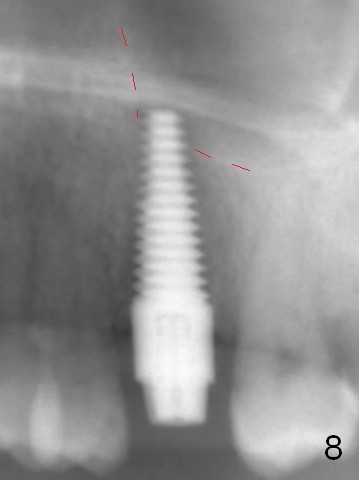

The septum perforates into the distobuccal socket when 4.3 mm drill is being used. The sinus floor bone (Fig.5 *, Fig.6-8 red dashed line) has to be used for primary stability. Finally a 6x20 mm tap achieves stability apparently by engaging to the mesial and distal walls of the socket (Fig.6). The insertion torque of a 6x20 mm tissue-level implant is > 60 Ncm (Fig.7) with allograft packed into the remaining socket (*).